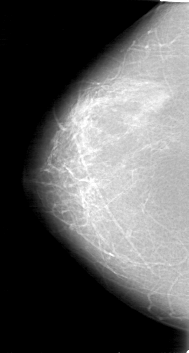

D_4039_1.RIGHT_CC

D_4039_1.LEFT_CC

RIGHT_CC LINES 5281 PIXELS_PER_LINE 2821 BITS_PER_PIXEL 12 RESOLUTION 43.5 NON_OVERLAY

FILE: D_4039_1.LEFT_CC.OVERLAY

TOTAL_ABNORMALITIES 1

ABNORMALITY 1

LESION_TYPE MASS SHAPE OVAL MARGINS OBSCURED

ASSESSMENT 0

SUBTLETY 5

PATHOLOGY BENIGN

TOTAL_OUTLINES 1

BOUNDARY